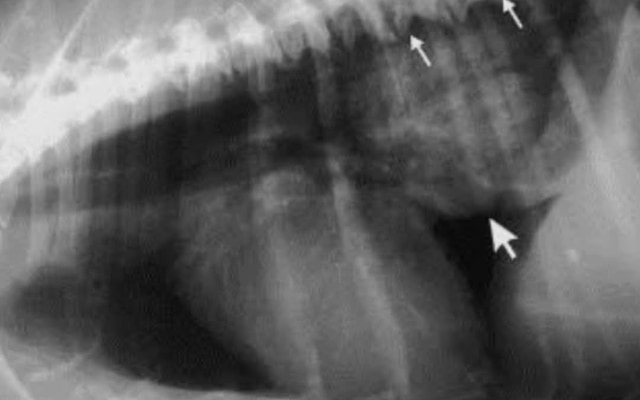

How is it diagnosed?

Through clinical history, signs, and imaging like endoscopy and X-rays.